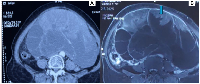

Six months earlier, she underwent an evaluation of abdominal pain in her hometown. Initial ultrasonography and CT scan revealed a right adnexal lesion: a well-defined, multiloculated cystic mass with air foci and septations (12 × 14 cm), provisionally diagnosed as a pelvic abscess (Figure 1A). She was advised by conservative management at that time.

On general examination, she appeared cachectic and pale. Abdominal examination revealed a 22 × 18 cm mass arising from the pelvis, extending to the upper abdomen, with a solid-cystic consistency, restricted mobility, and no tenderness. Pelvic examination revealed a hypertrophied cervix and an adnexal mass filling the abdomen. MRI pelvis demonstrated a large, multiloculated solid-cystic lesion (24 × 16 × 27 cm) arising from the right adnexa, extending up to the renal hilum. Solid components were T2 hyperintense with diffusion restriction. There were no peritoneal or para-aortic deposits, no significant lymphadenopathy, and only mild ascites (Figure 1B).

Figure 1

Radiological imaging of the abdominal lesion.

( A) CT axial view showing a large, lobulated, multiloculated solid cystic lesion in abdomen. ( B) MRI T2 Image showing a large, lobulated, multiloculated solid cystic lesion in abdomen with hyperintense solid components (arrow).

Figure 1: Radiological imaging of the abdominal lesion.